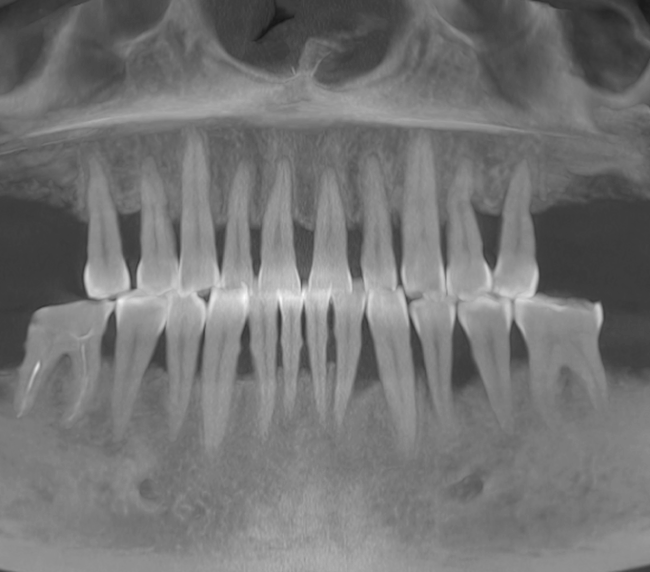

- Consultație, radiografie și plan de tratament personalizat

- Șlefuirea dinților de susținere sau inserarea implanturilor

- Ai unul sau mai mulți dinți lipsă într-o zonă în care dinții vecini sunt sănătoși și stabili